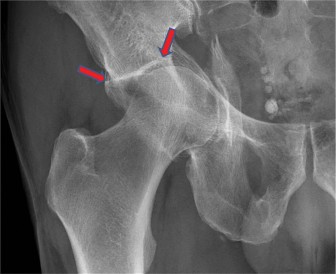

A 73-year-old man with a history of hypertension and hyperlipidemia presents to your office with right hip pa…